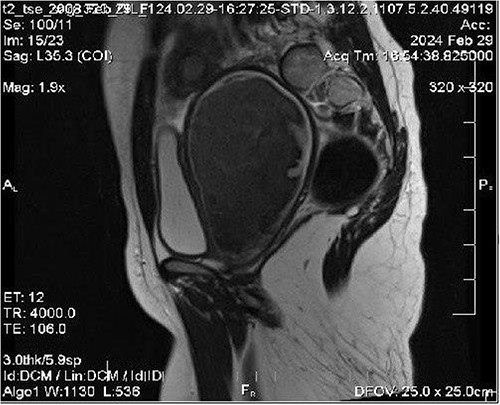

We ordered an MRI with contrast injection to assess the ultrasound findings, which showed a big pelvic cystic hematoma measuring (7 × 12 × 6.7 cm) in the left paracentral position that extends close to the vaginal opening to the level of the right adnexa, encircled by a regular, thick wall that did not luminesce, and a relatively small myometrium with a regular endometrium (Fig. 1). It also shows the level of vaginal obstruction (Fig. 2).

MRI imaging showing a big pelvic cystic hematoma measuring (7 cm × 12 cm × 6.7 cm) in the left paracentral position that extends close to the vaginal opening to the level of the right adnexa, encircled by a regular, thick wall that did not luminesce, and a relatively small myometrium with a regular endometrium.